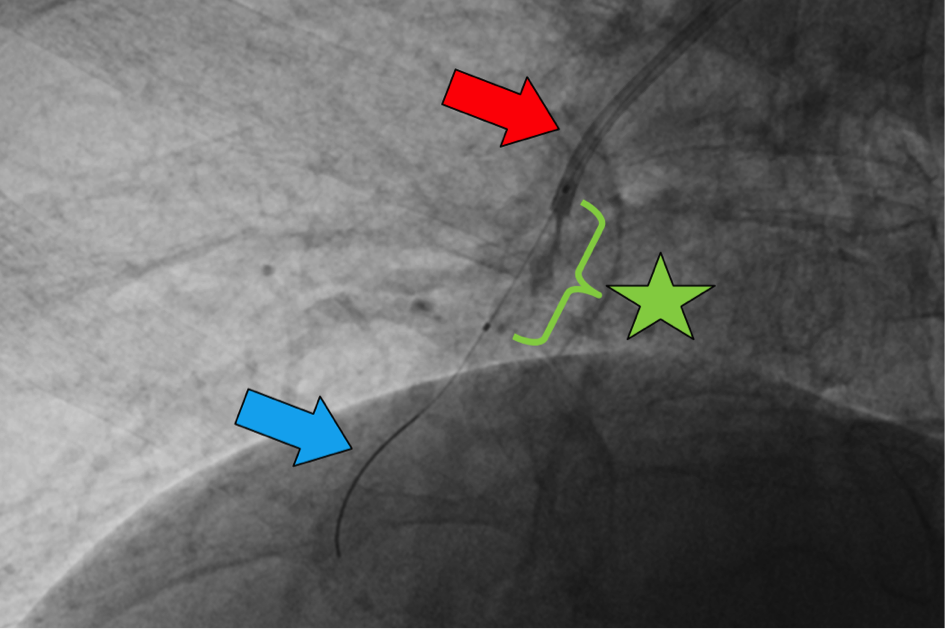

Seit über 15 Jahren werden weltweit in wenigen erfahrenen Zentren Patienten mit nicht-operabler CTEPH Katheter-gestützt mittels pulmonalarterieller Ballonangioplastie (BPA) therapiert. Im Bereich der Therapie der CTEPH mittels Ballonkatheter sind Zentren aus Japan und Europa weltweit führend. Im Frühjahr 2012 haben wir in der Interventionellen Radiologie der MHH in enger Kooperation mit der Pneumologie als erstes Zentrum Lungengefäßerweiterungen mittels Ballonkatheter in Deutschland durchgeführt. Mit Hilfe der BPA können Veränderungen der Lungenarterien, die in kleinsten Lungenarterien lokalisiert sind, mittels eines Führungsdrahtes passiert und anschließend mit einem Ballon aufgedehnt werden (Bild 1). Die Behandlung beschränkt sich auf Grund von möglichen Komplikationen auf einzelne Lungenarterien in umschriebenen Anteilen der Lungen. Deshalb sind zur Behandlung der gesamten pulmonalarteriellen Strombahn mehrere Therapiesitzungen erforderlich. Für den Eingriff ist in der Regel nur ein Krankenhausaufenthalt von wenigen Tagen erforderlich. Am ersten Tag erfolgen die Aufnahme im Krankenhaus und die Aufklärung für den Eingriff, sowie die Kontrolle von Blutwerten. Am zweiten Tag findet der Eingriff statt. Im Anschluss erfolgt eine Überwachung auf Station und in der Regel in den folgenden Tagen die Entlassung.

Die BPA wird am wachen Patienten durchgeführt, u.a. da der Patient bestimmte Atemkommandos befolgen muss. Mittels sonographisch-gesteuerter Punktion einer Leistenvene wird ein temporärer Zugang zum venösen Gefäßsystem geschaffen. Hierüber wird ein Führungskatheter in die pulmonalarterielle Strombahn eingeführt und über diesen Führungskatheter werden der Ballonkatheter und der zugehörige Führungsdraht eingebracht (Bild 2).

Entsprechend der vorab in der hochaufgelösten 3D Planung der Lungenarterienstrombahn zur Therapie ausgewählten Zielgebiete werden die geplanten Segmentarterien gezielt mit einem Draht sondiert und anschließend die Befunde mit speziellen Ballons behandelt (Bild 5).